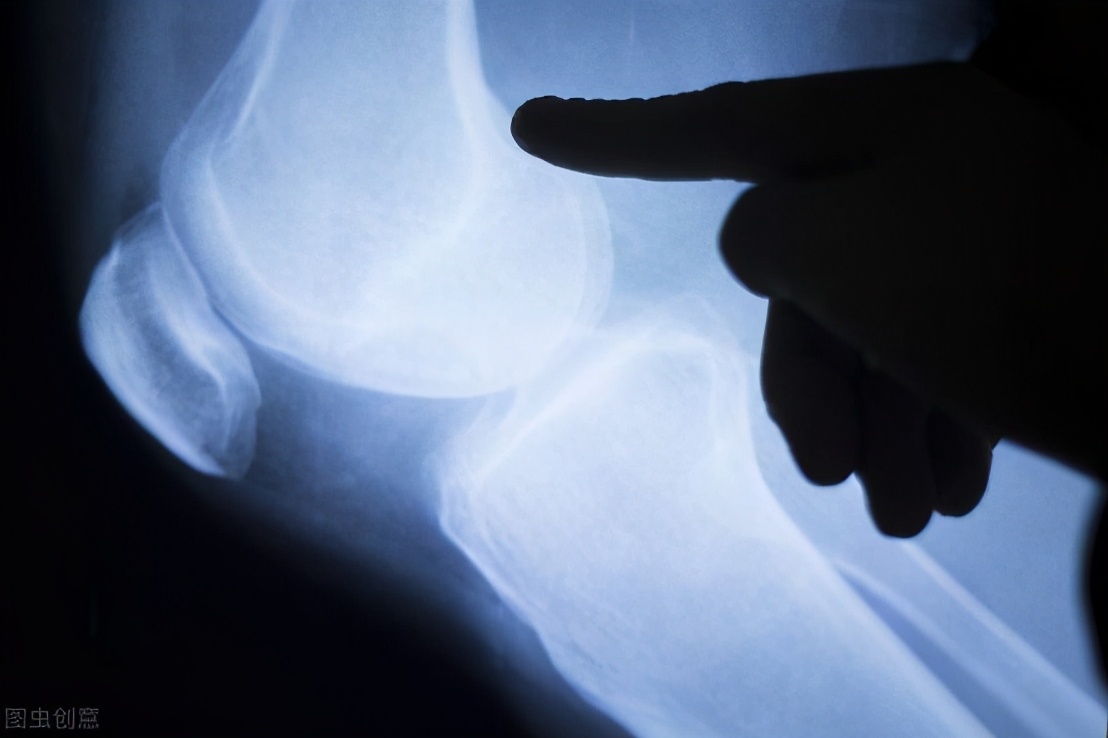

膝关节作为人体的重要关节,不仅承受着身体的重量,还维持着下肢的活动,相比其他关节更加脆弱。多数运动者往往不注重保护膝关节,从而出现韧带损伤、半月板损伤、滑囊炎和骨关节炎等多种运动损伤。

跑步、登山等运动,其实都是做重复的屈曲伸直动作,会使髌骨、胫骨与股骨承受巨大压力,长期如此,容易引起膝关节损伤。当你有如下表现时,就要警惕是不是自己的膝盖出现问题了: